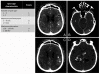

Clinical applications of the computed tomography angiography spot sign in acute intracerebral hemorrhage: a review